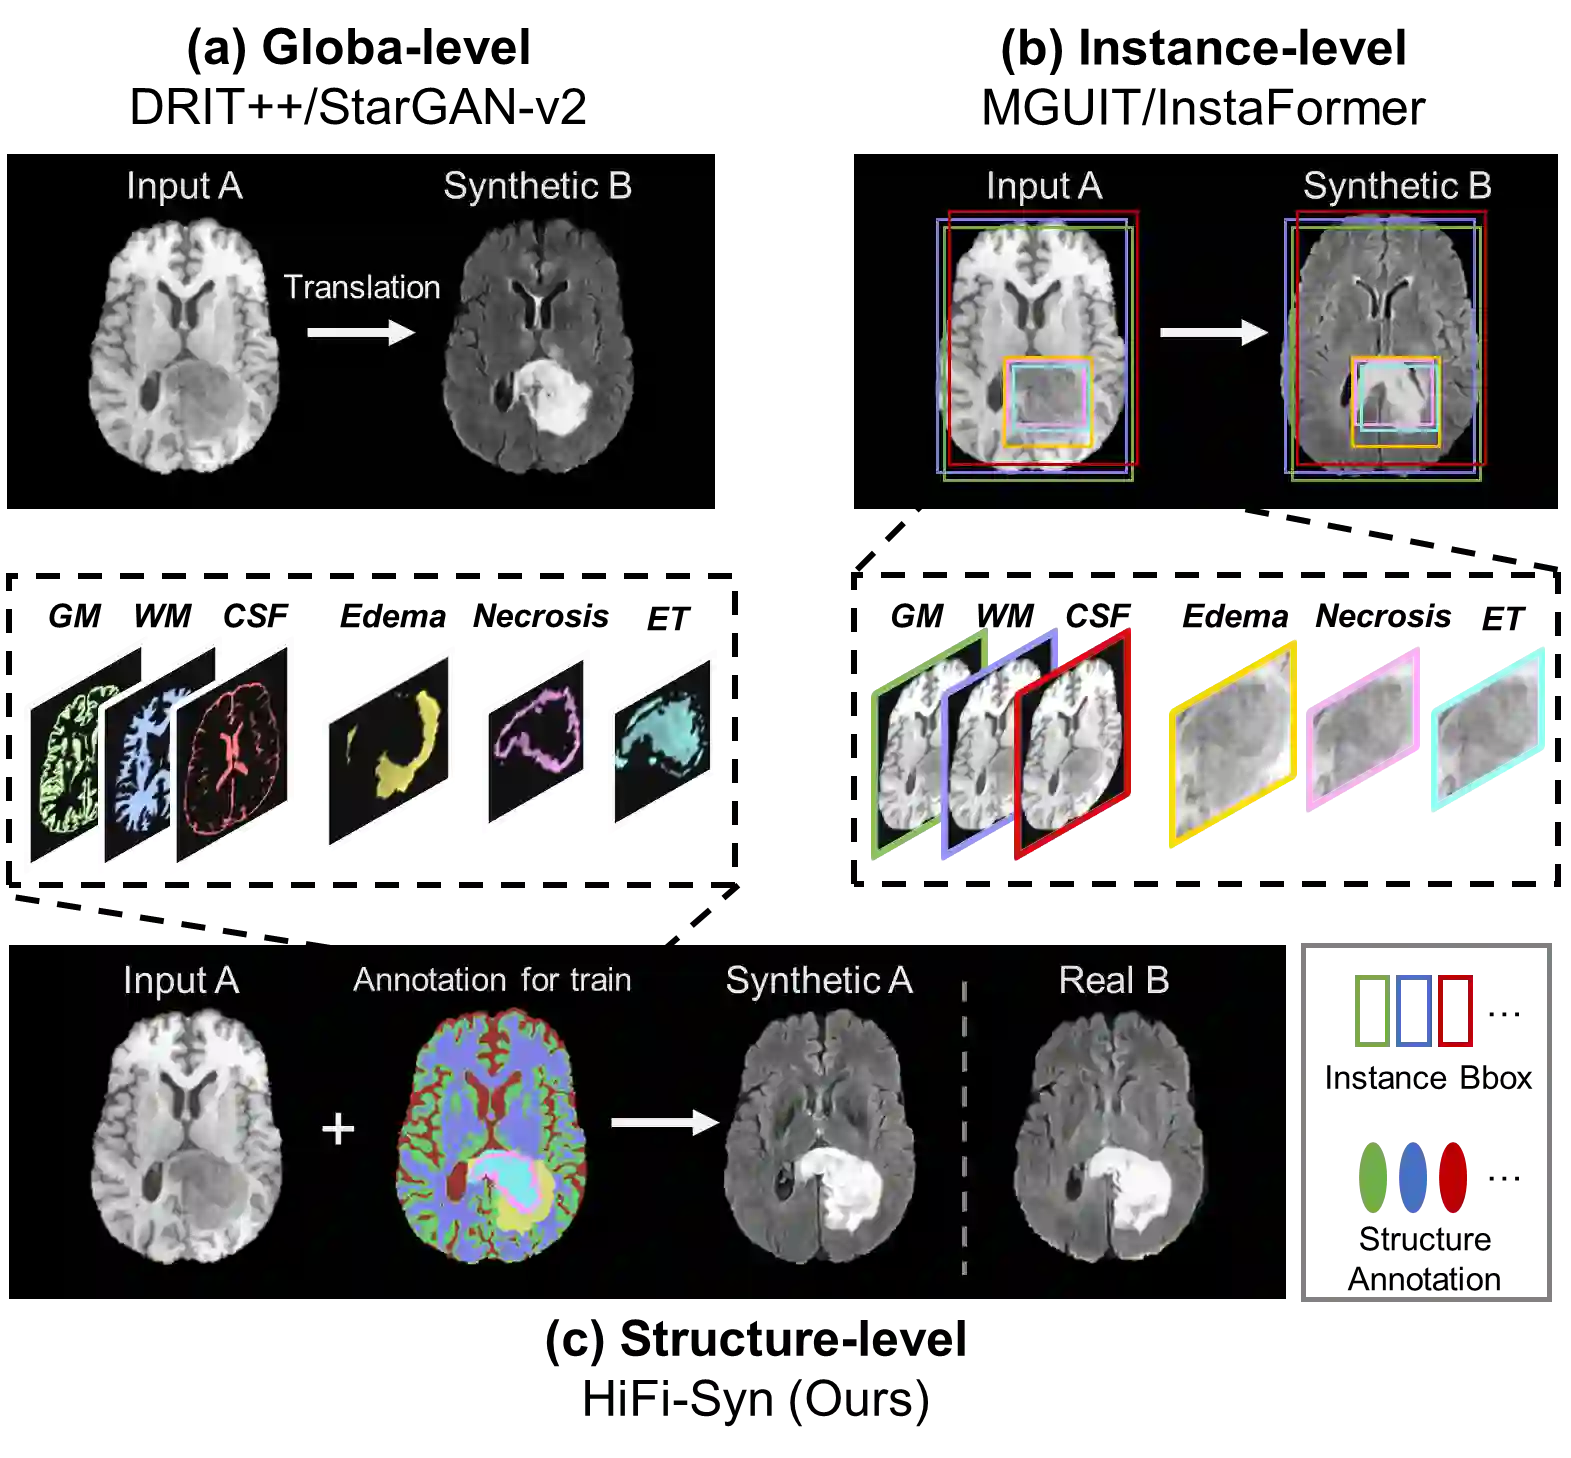

Synthesizing medical images while preserving their structural information is crucial in medical research. In such scenarios, the preservation of anatomical content becomes especially important. Although recent advances have been made by incorporating instance-level information to guide translation, these methods overlook the spatial coherence of structural-level representation and the anatomical invariance of content during translation. To address these issues, we introduce hierarchical granularity discrimination, which exploits various levels of semantic information present in medical images. Our strategy utilizes three levels of discrimination granularity: pixel-level discrimination using a Brain Memory Bank, structure-level discrimination on each brain structure with a re-weighting strategy to focus on hard samples, and global-level discrimination to ensure anatomical consistency during translation. The image translation performance of our strategy has been evaluated on three independent datasets (UK Biobank, IXI, and BraTS 2018), and it has outperformed state-of-the-art algorithms. Particularly, our model excels not only in synthesizing normal structures but also in handling abnormal (pathological) structures, such as brain tumors, despite the variations in contrast observed across different imaging modalities due to their pathological characteristics. The diagnostic value of synthesized MR images containing brain tumors has been evaluated by radiologists. This indicates that our model may offer an alternative solution in scenarios where specific MR modalities of patients are unavailable. Extensive experiments further demonstrate the versatility of our method, providing unique insights into medical image translation.